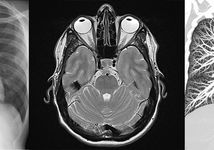

Ab sofort bieten wir Ihnen einen direkten Zugang zu Ihren Bildern an. Damit haben Sie überall und jederzeit Zugriff auf Ihre Bilder und können z.B. einfach weitere behandelnde…

Kontrastmittel verbessern die Aussagekraft einer MRT erheblich und können sogar entscheidende Informationen zutage bringen. Kontrastmittel, die Gadolinium enthalten, werden dabei…

Als erste und aktuell einzige Praxis in Karlsruhe bieten wir unseren Patientinnen die Möglichkeit zur Tomosynthese der Brust. Damit kann mit weniger Strahlendosis als bislang eine…